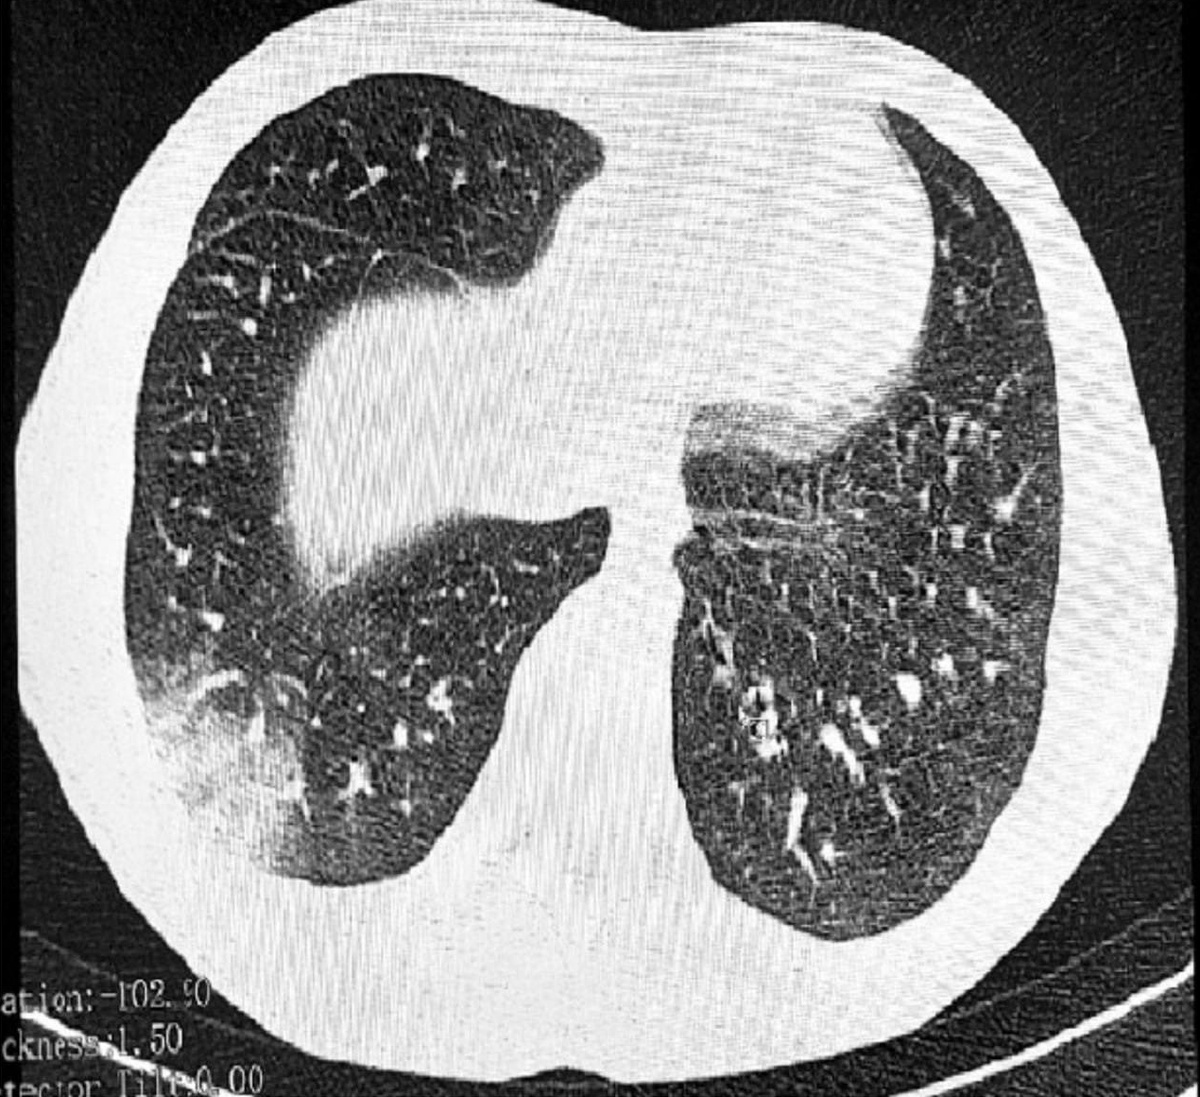

Снимок из открытых источников

В Российской Федерации впервые были зарегистрированы случаи заболевания, связанного с курением электронных сигарет, которое в США известно как EVALI (повреждение легких, связанное с использованием электронной сигареты или продукта vaiping). Это очень серьезное заболевание легких человека, которое характеризуется тяжелым воспалением и рубцеванием мелких бронхов (бронхиол) легких.

В Томске у двух подростков были обнаружены последствия: у одного - облитерирующий бронхиолит (форма EVALI), а у другого - отравление центральной нервной системы, вызванное курением смесей для электронных сигарет.

Заболевание трудно диагностировать, но одним из ярких симптомов являются характерные хрипы в легких, напоминающие звук лопающегося попкорна. Из-за этого заболевание получило еще одно название - "попкорновая болезнь".

На данный момент, к сожалению, не существует эффективного лечения EVALI. Ситуация требует пристального внимания и дальнейшего изучения причин и последствий использования электронных сигарет, особенно среди подростков. Но одно уже можно сказать точно: отказ от так называемого "парения" поможет сохранить человеку свои легкие. Берегите себя!